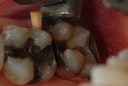

Alan Chinn #31 pre-op

Alan Chinn #31 buccal view